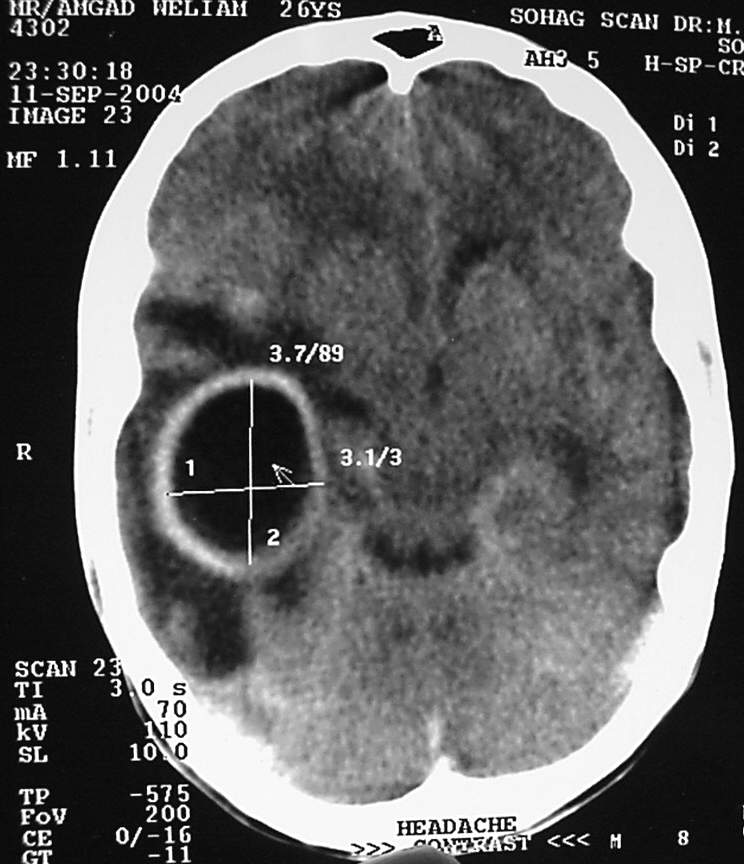

Ear Clinical Photos for Static Stations